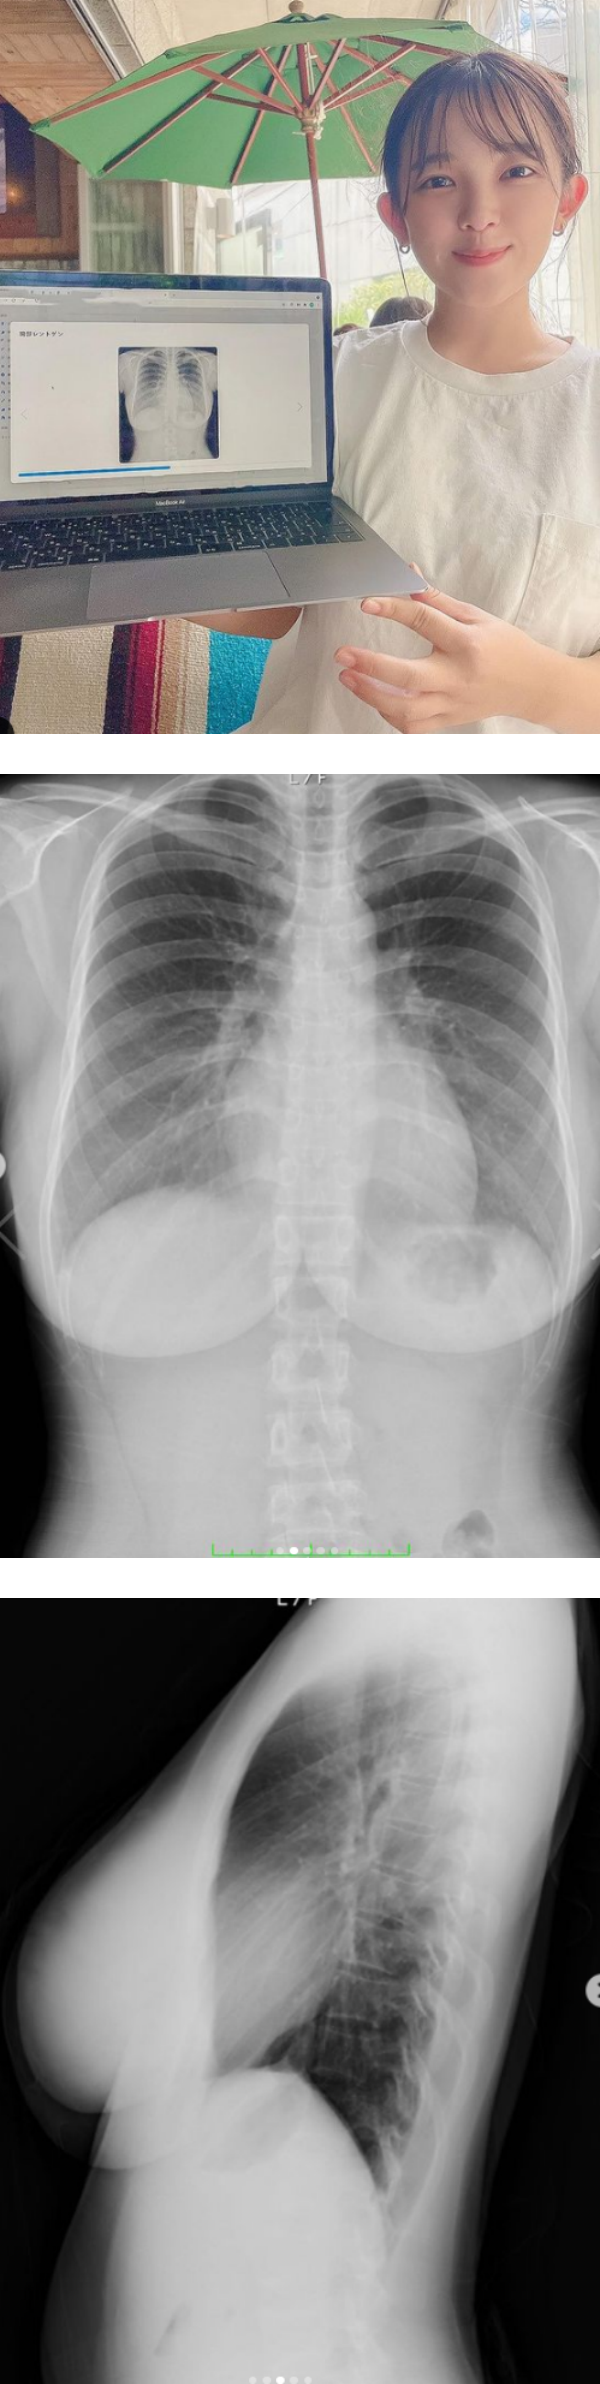

日本25岁写真偶像天木纯(天木じゅん)拥有甜美脸蛋以及I罩杯的惊人上围,她近期晒出上半身的X光片,直接用证据打脸质疑她是假奶的酸民。

天木纯18日在IG晒出一组自己的X光片,包括正面、侧面以及两边乳房的特写照。她特别提到X光片中右胸部分有影子是胃泡,而透过X光片可看出她的胸部是纯天然,没有任何填充物。

据悉,天木纯因为I罩杯被日媒封为“战舰级雪乳”,但也因此引来不少质疑她是假奶的酸民。此次她直接晒出X光片自证清白,同时也透过健康检查得知自己的体检数值一切正常,比2年前更健康。